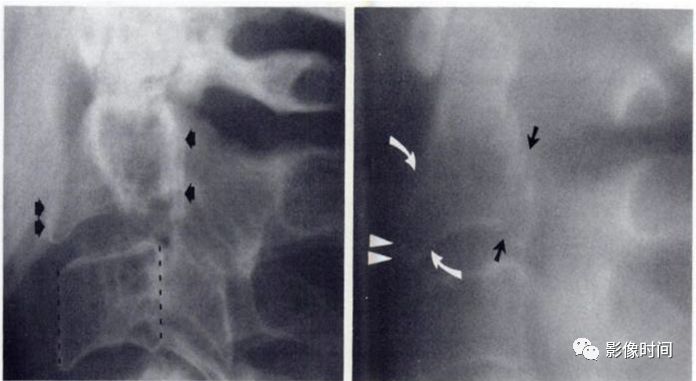

2裸面征

裸面征(naked facet sign),又称反汉堡面包征(reverse hamburger bun sign)

当脊椎小关节脱位时,上关节突脱位可位于上关节突后方,关节面向下显露,表现为关节面裸露,为裸面征(黄箭)。脱位可单侧或双侧出现;本例为左侧脱位,右侧为半脱位:可见上关节突(红箭)外移,相对下关节面显露,表现为关节面部分裸露(白箭之间)。

这是屈曲分离型损伤的特点,提示有严重的韧带损伤和脊柱不稳。

上图为 45 岁男性,交通事故后行轴位 CT 检查。显示右侧颈椎汉堡包征异常。双侧关节突不同程度分离、移位。

典型病例

正常汉堡包征的小关节(下图);外伤后,CT 骨窗示其前部「面包」(上关节突,黑箭)后移,位于下部「面包」(下关节突,白箭)的后方,关节面裸露。

引用自:https://radiopaedia.org/articles/naked-facet-sign-vertebral-column